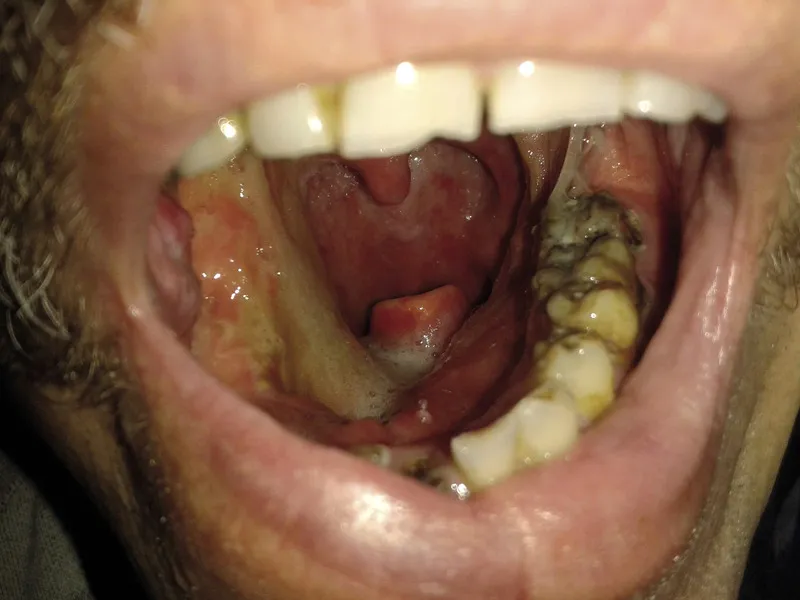

Rak dna jamy ustnej może manifestować się różnorodnymi objawami, które są kluczowe dla wczesnej diagnozy. Wczesne objawy mogą być subtelne i nie zawsze łatwe do zauważenia. Często pacjenci nie zwracają na nie uwagi, co może prowadzić do opóźnienia w leczeniu. W miarę postępu choroby objawy stają się bardziej wyraźne i mogą znacząco wpływać na jakość życia pacjenta.

W późniejszych stadiach choroby objawy mogą obejmować silny ból, trudności w połykaniu oraz mowie, a także inne poważne dolegliwości. Dlatego ważne jest, aby regularnie monitorować stan zdrowia i nie ignorować żadnych niepokojących sygnałów. W przypadku wystąpienia jakichkolwiek objawów, takich jak zmiany w jamie ustnej, warto skonsultować się z lekarzem.

Wczesne objawy raka dna jamy ustnej mogą obejmować utrzymujący się ból gardła, owrzodzenia w jamie ustnej oraz nieuzasadnione zmiany w wyglądzie błony śluzowej. Pacjenci mogą zauważyć, że pojawiają się białe lub czerwone plamy, które nie znikają. Często występują również trudności w przełykaniu, które mogą być mylone z innymi dolegliwościami. Ważne jest, aby nie bagatelizować tych objawów, ponieważ mogą one wskazywać na poważne problemy zdrowotne.- Utrzymujący się ból w obrębie jamy ustnej, który nie ustępuje po standardowym leczeniu.

- Owrzodzenia, które nie goją się w ciągu kilku tygodni.

- Nieuzasadnione zmiany w kolorze błony śluzowej, takie jak białe lub czerwone plamy.